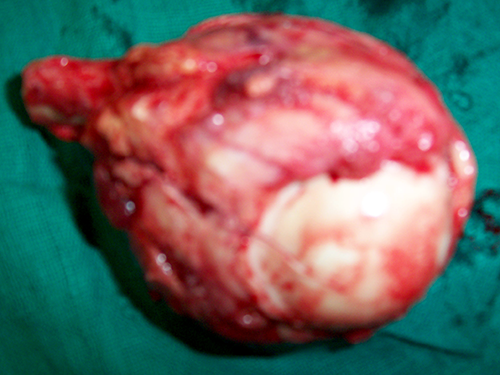

Specimen